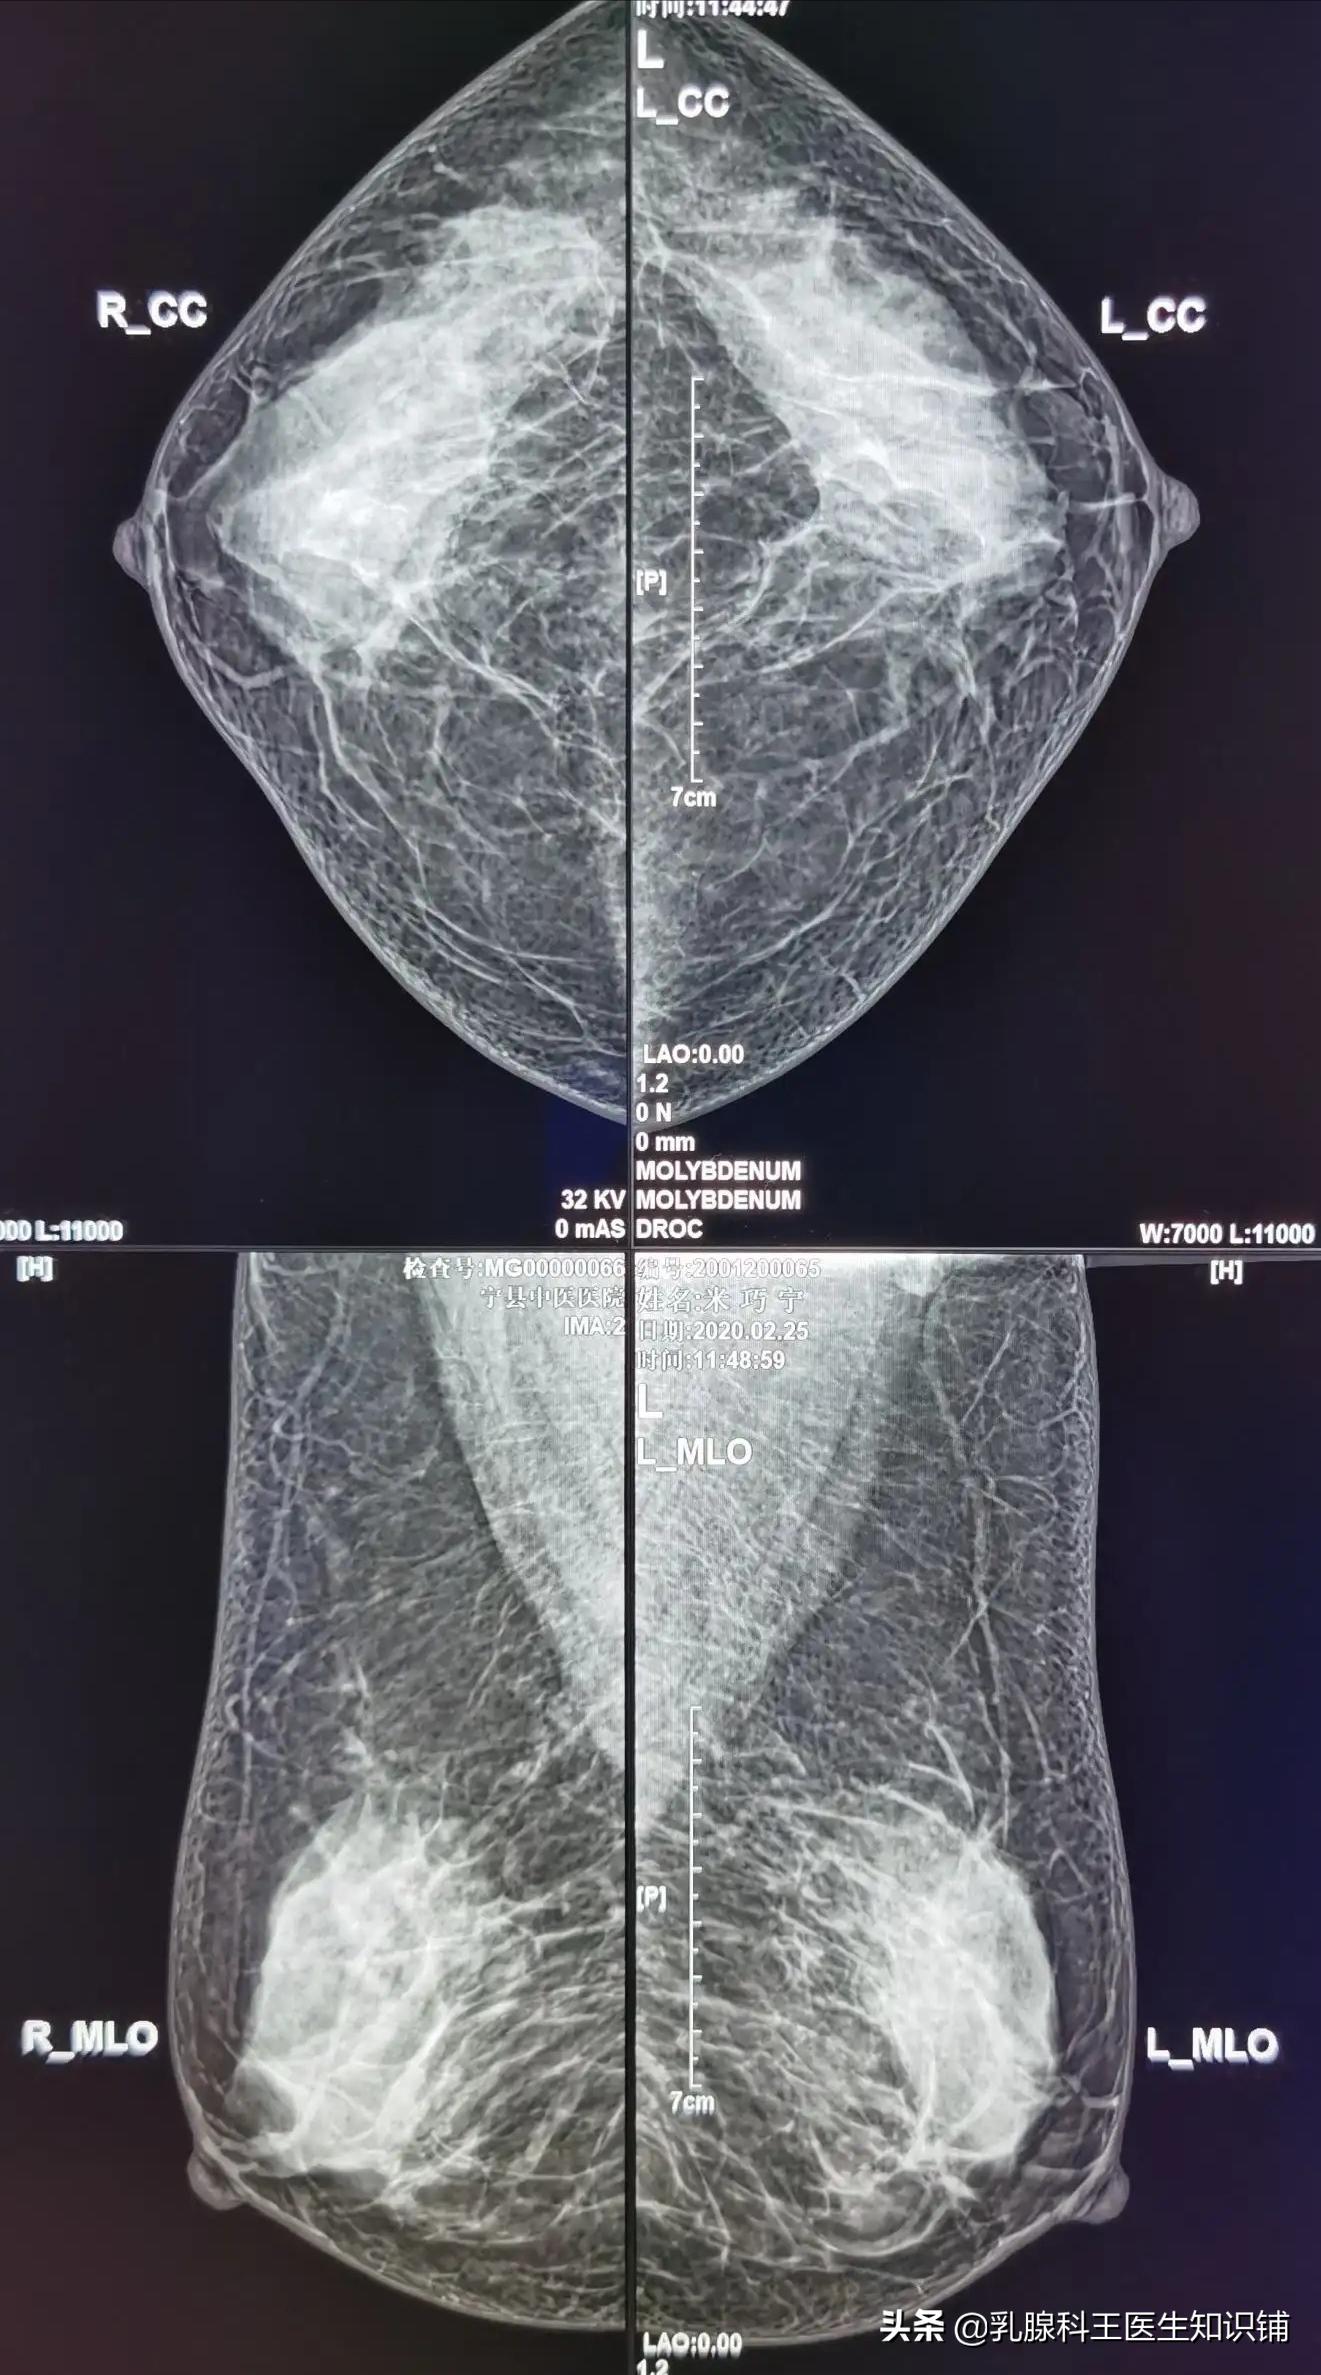

4、乳房X线摄片:行乳房X摄片可查出导管原位癌,其主要表现为导管影增厚及微小钙化点;选择性乳腺导管造影对导管扩张症或乳房囊性增生病以及乳腺导管内乳头状瘤有诊断价值。此检查为X线检查,有一定的放射性,不建议小于40岁女性作为常规检查。

乳腺钼靶